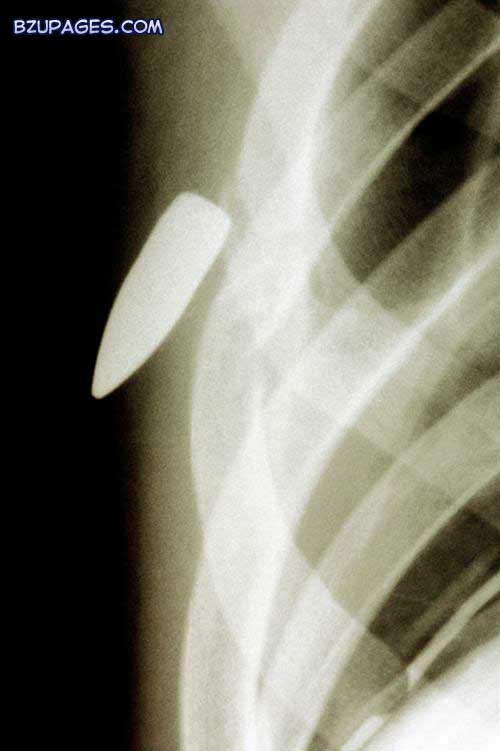

Attachment 21989

An X-ray of a bullet (conical object at centre left) embedded in the chest of a patient